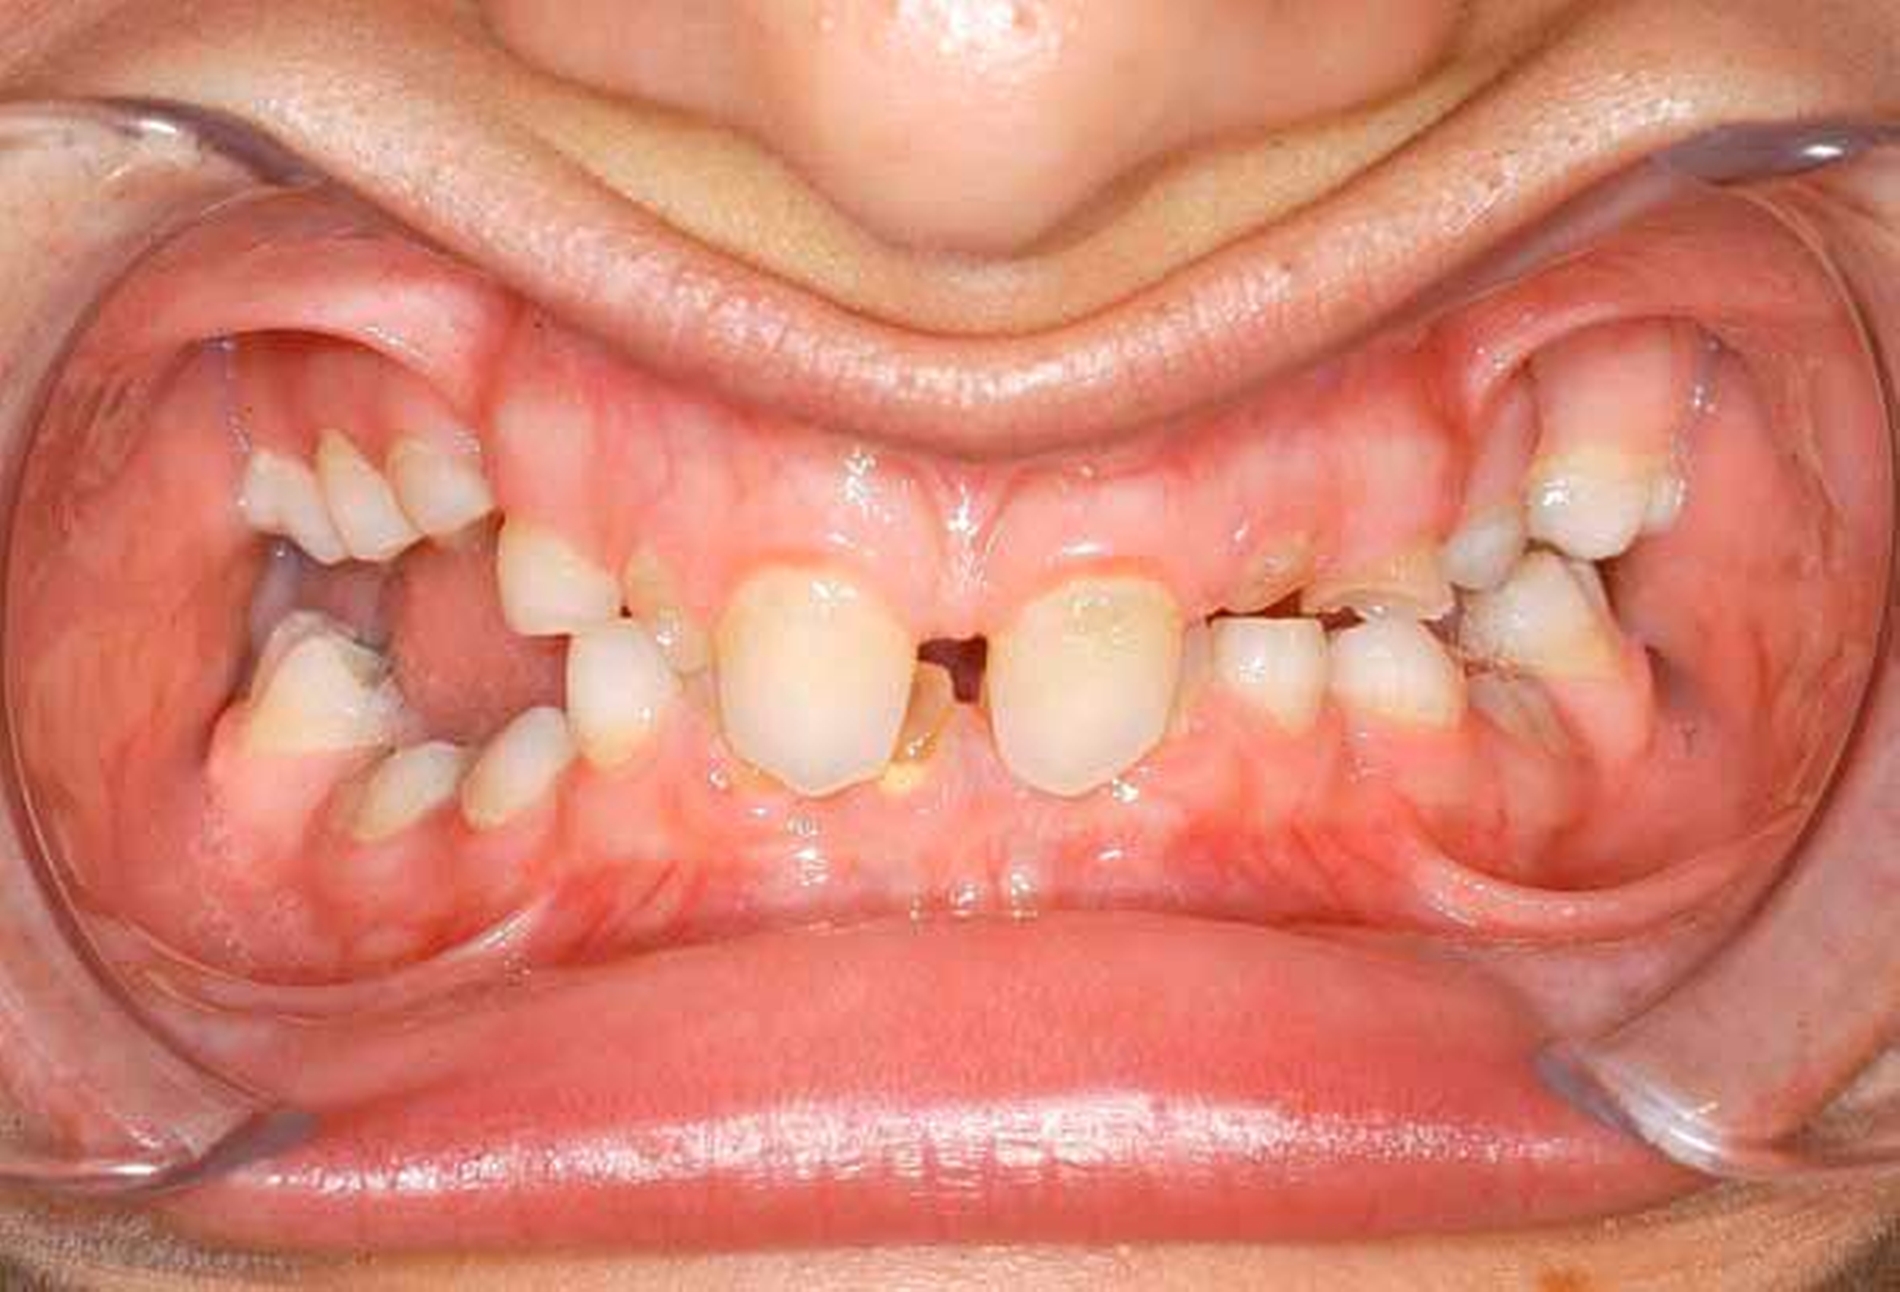

Ein dreijähriges Mädchen wird mit einem beginnenden Abszess der linken Fossa canina vorstellig. Klinisch zeigen die Zähne keinerlei kariöse Läsionen, die Ursache ist unklar. Radiologisch fällt ein ausgedehntes Pulpenhorn am Zahn 63 auf. Die Patientin ist insgesamt für ihr Alter eher kleinwüchsig. Allgemein anamnestisch liegt eine X-chromosomale Hypophosphatämie (Phosphatdiabetes) vor.

In histologischen Untersuchungen von Zähnen findet sich bei der X-chromosomalen Hypophosphatämie Interglobulardentin. Dies bedeutet, dass im Dentin eine unvollständig mineralisierte Dentinmatrix zwischen regulär mineralisierten Globuli vorliegt. Daneben fallen in histologischen Untersuchungen Ausdehnungen der Pulpa mit Pulpenhörnern und vergrößerten Pulpenkaven auf, die sich bis an die Schmelz-Dentin-Grenze ausdehnen, was eine Infektion der Pulpa begünstigt (Abbildung).

Infolge von Attrition des Zahnschmelzes können Bakterien durch das fehlgebildete und in seiner Struktur durchlässige Dentin in die bis an die Schmelz-Dentin-Grenze verzweigte Pulpa eindringen und zu Pulpanekrosen und Abszessen führen.